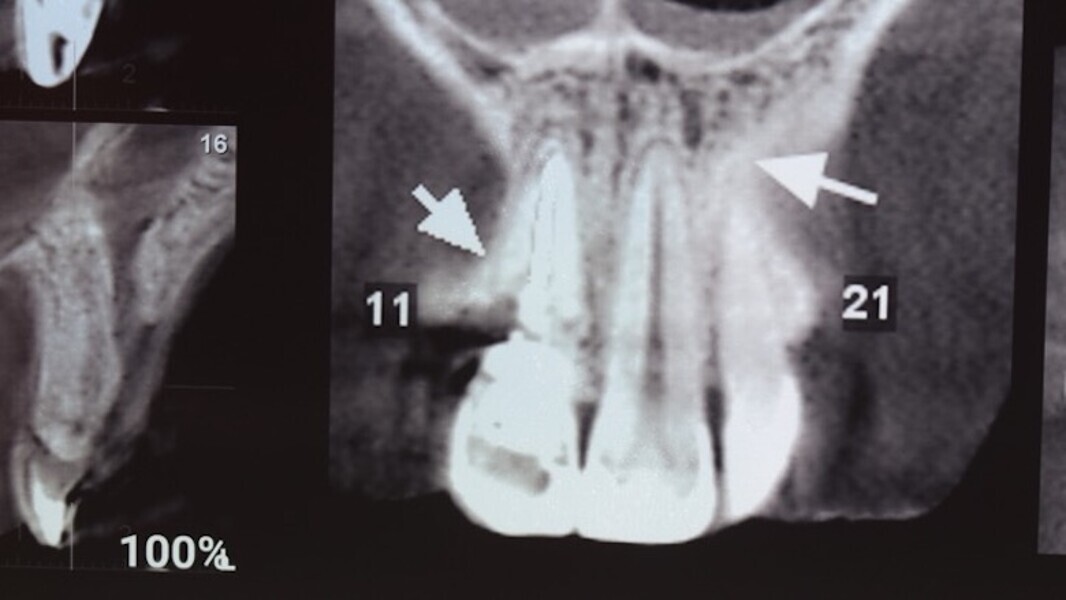

Figuras 2 y 3. Imágenes de tomografía CBCT donde se observa el grado de destrucción de la pared vestibular.